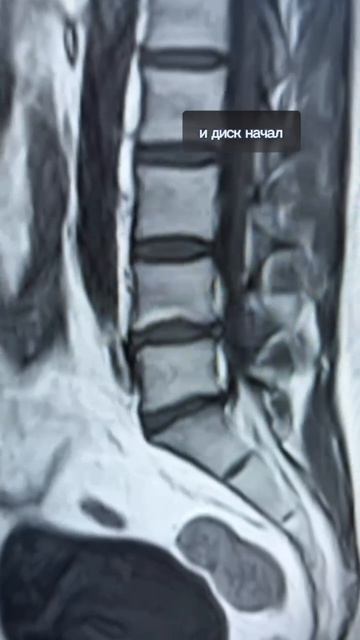

На них можно выявить важные детали влияющие на диагностику и лечение. На данном МРТ мы видим что межпозвонковые диски в норме по их цвету.

Однако также вероятно наличие спондилодезита или спондилоартроза на нижних позвонках что изменяет суставные поверхности. Тщательный анализ изображений ключ к точной диагностике и эффективному лечению!